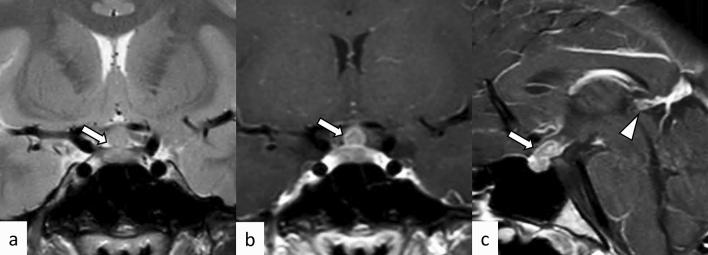

垂体炎的神经影像学:病因和影像模拟。

Neuroimaging of hypophysitis: etiologies and imaging mimics.

Hypophysitis is an inflammatory disease affecting the pituitary gland. Hypophysitis can be classified into multiple types depending on the mechanisms (primary or secondary), histology (lymphocytic, granulomatous, xanthomatous, plasmacytic/IgG4 related, necrotizing, or mixed), and anatomy (adenohypophysitis, infundibulo-neurohypophysitis, or panhypophysitis). An appropriate diagnosis is vital for managing these potentially life-threatening conditions. However, physiological morphological alterations, remnants, and neoplastic and non-neoplastic lesions may masquerade as hypophysitis, both clinically and radiologically. Neuroimaging, as well as imaging findings of other sites of the body, plays a pivotal role in diagnosis. In this article, we will review the types of hypophysitis and summarize clinical and imaging features of both hypophysitis and its mimickers.

垂体炎是一种影响垂体的炎症性疾病。根据发病机制(原发性或继发性)、组织学(淋巴细胞性、肉芽肿性、含铁血黄素沉积性、浆细胞/IgG4 相关性、坏死性或混合性)和解剖学(腺垂体炎、漏斗神经垂体炎或全垂体炎),垂体炎可分为多种类型。适当的诊断对于治疗这些潜在危及生命的疾病至关重要。然而,生理形态改变、残留物以及肿瘤性和非肿瘤性病变可能在临床上和影像学上表现为垂体炎。神经影像学以及身体其他部位的影像学表现对诊断起着关键作用。本文将回顾垂体炎的类型,并总结垂体炎及其类似物的临床和影像学特征。